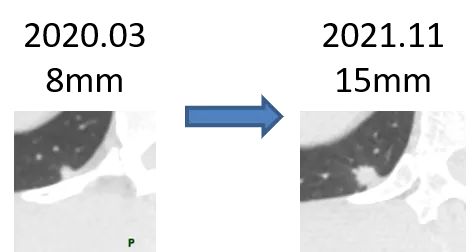

良性結節通常是惰性的,不會長大,還有很多炎性結節可以吸收消失。而惡性結節會緩慢生長。

所以,對於拿不準的結節,我們可以採用隨訪觀察的方式,來判斷它的良惡性。

要是吸收了——恭喜你!是良性結節!

要是不變——嗚~良性概率大,建議繼續隨訪。

要是增大了——考慮惡性可能,建議手術切除。

明顯增大的實性肺結節,考慮惡性

當然這也不是絕對的,有些惡性結節可能暫時不會變化,也有一些良性結節增長非常迅速,比如炎性病灶。不過,增長變大總歸是一個非常不好的特徵,需要密切關注。

正如把犯罪嫌疑人放掉,可能導致他繼續犯罪一樣,隨訪也有一定的風險,就是惡性結節的進展和轉移,這就要求我們根據情況合理制定隨訪時間,不能太短,太短了看不出變化,也不能太長,太長真的有可能導致腫瘤進展。